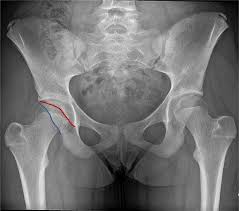

고관절 통증이 나타나는 위치

고관절 통증은 엉덩이 깊숙한 부위에서만 느껴진다고 생각하기 쉽지만, 실제로는 다양한 위치로 퍼져 나타날 수 있습니다.

특히 사타구니 통증은 고관절 이상을 가장 강하게 의심할 수 있는 신호로 전문가들도 중요하게 보는 증상입니다.